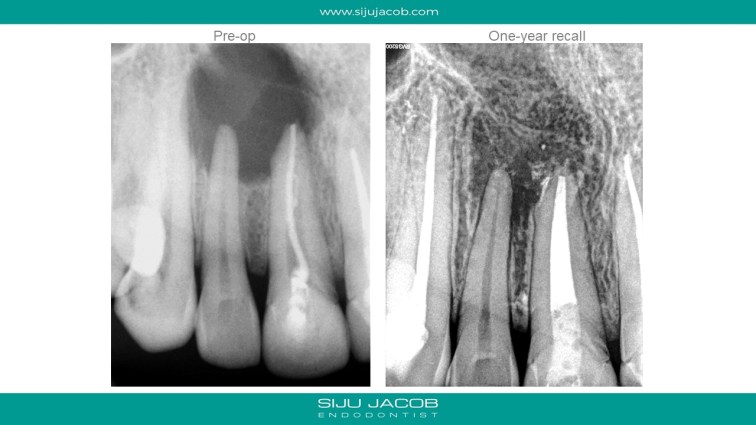

This patient had a large lesion in the right maxillary anterior region. The lateral Incisor tested vital. I decided to re-treat only the central Incisor. Despite several calcium hydroxide changes spread over 2 months, there was persistent drainage of pus. Instead of opting for the more radical option of endo on the lateral and immediate surgery, we decided to do decompression. The drainage stopped and the tooth was subsequently obturated. Patient recently came for some other work and I took a 5-year recall raiograph. It seems to be holding on for now. I was tempted to do the endo on the lateral on several occasions, but it always tests vital.